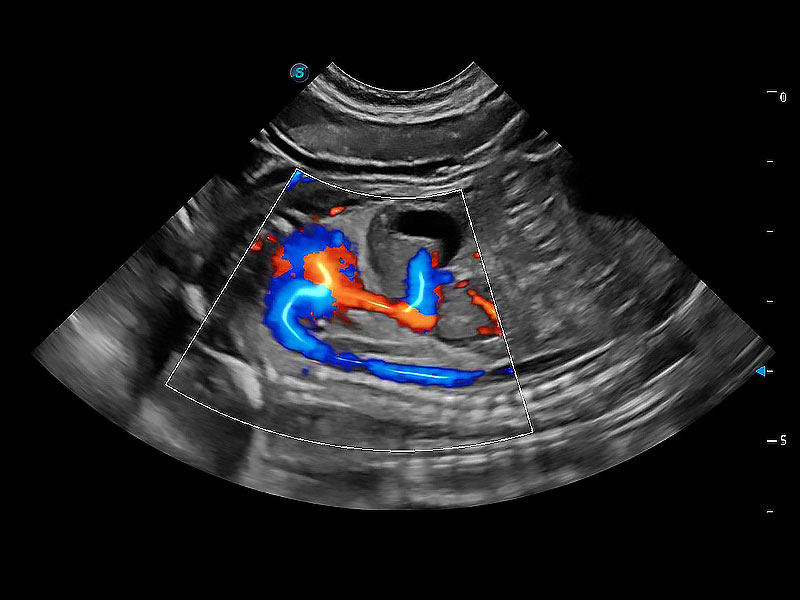

在传统二维血流成像的基础上,呈现血流的立体感,具有动感的生命力之美。即便是微小的血管也能轻松应对,提高了血流的视觉敏感性。